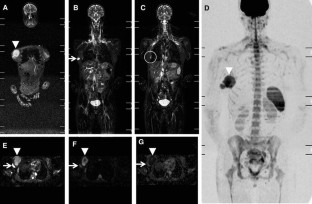

Fig. 2